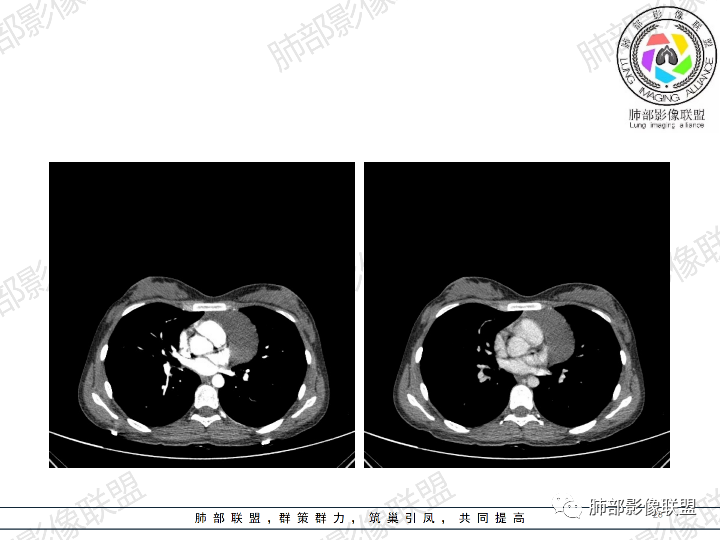

年轻女性,体检发现纵隔肿块。

影像:前纵隔一实性肿块,形态不规则,沿主动脉间隙生长,部分包绕大血管,边界欠清,周围脂肪间隙消失,平扫密度尚均匀,增强扫描大部分强化不明显,病灶左下部分似有高强化,强化病灶与血管分界清楚,考虑:1淋巴瘤(一般居中,病灶较软,包绕血管)

女性,23岁,体检发现纵隔占位。CT示前纵隔不规则占位,沿间隙生长,局部包绕大血管及心包,增强内部可见部分区域呈明显渐进性强化,其余部分强化不明显,考虑囊性畸胎瘤或神经鞘瘤>淋巴瘤,太年轻不考虑胸腺瘤

青年女性患者,体检发现左前纵隔占位性病变,胸部CT:左前纵隔见一不规则占位性病变,整体边界清楚,紧贴血管,间隙不明显,内部密度尚均匀,未见钙化及脂肪密度,增强扫描不均匀轻度强化,总体考虑偏良性病变,胸腺增生?

23岁女性

无症状

这个病灶有点怪

1、形态,似乎与常规肿瘤不一致

2、有间隔

3、密度强化有点怪

这些边缘收缩

符合胸腺正常形态

这是腺体内的一个囊性病变:

这是腺体内的另一个

南边:

倾向于:一个正常增大的腺体内的病变

根据部位:腺体首先考虑胸腺,其次才考虑异位结构

胸腺内囊、实性占位

首先支持胸腺增生并感染

其次胸腺瘤

然后才考虑异位的病变

这个病例的特点就是病灶整体符合胸腺的形态,如果它是肿瘤,它周围侵袭性不明确的话,它应该膨隆的挺厉害,它单纯就是一个膨隆性生长的,那么它就应该是类圆形的,边缘应该是膨大的,但是这个病例不是,有些地方边缘是收缩的,那么就是原有的胸腺基础上内部出了问题,里面强化增生明显就有可能是在原有胸腺基础上里面滋生出来一个病变。年龄确实年轻,又是女性。胸腺里面的病例多是胸腺瘤、胸腺癌、淋巴瘤。既然定的是胸腺里面的病变,那么就在这里面考虑。淋巴瘤首先不是。那么就是胸腺瘤和胸腺增生,胸腺囊肿的说法也有很多,因为胸腺增生里面有一种就是囊性的增生,里面有些地方有强化,囊肿合并感染了可以有,慢性炎性的肉芽肿的可以有强化。不能排除胸腺瘤,胸腺瘤放后面,一个原因就是太年轻了。如果考虑胸腺瘤,年龄不太符合,心里不踏实。我认为大家不考虑胸腺瘤是正常的思维,写报告也是待排,放第一诊断不合适。考虑有胸腺瘤是因为强化,占位效应,间隔。